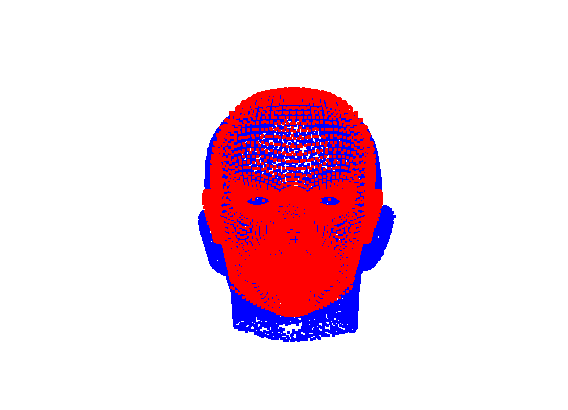

The template mesh is then warped in a global affine sense, as shown in Fig. 27 to minimise the least-squares error between the two sets of landmarks, when the head scan is fixed in its canonical poose. After this initial stage, landmarks and pseudo-landmarks are used in the same way as any other mesh vertex, as they are potentially noisy, as seen in earlier results analysis. This contrasts with Amberg et al’s [11] approach where the influence of landmarks is gradually faded out.

|

|

Following this, OSNR ICP iterates over a set of decreasing mesh stiffnesses (typically 10), until the registration between the template and the scan is below some error or a maximum number of iterations is reached. Figure 28 shows a selection of template warp results. The template appears to be accurately warped onto the scan, at least in the normal direction of the surfaces, it is not possible to see error tangential to the surface. Furthermore, we have noted errors on some scans on the ears. To improve these we need a method of automatically landmarking the ears, which is an area for further work.